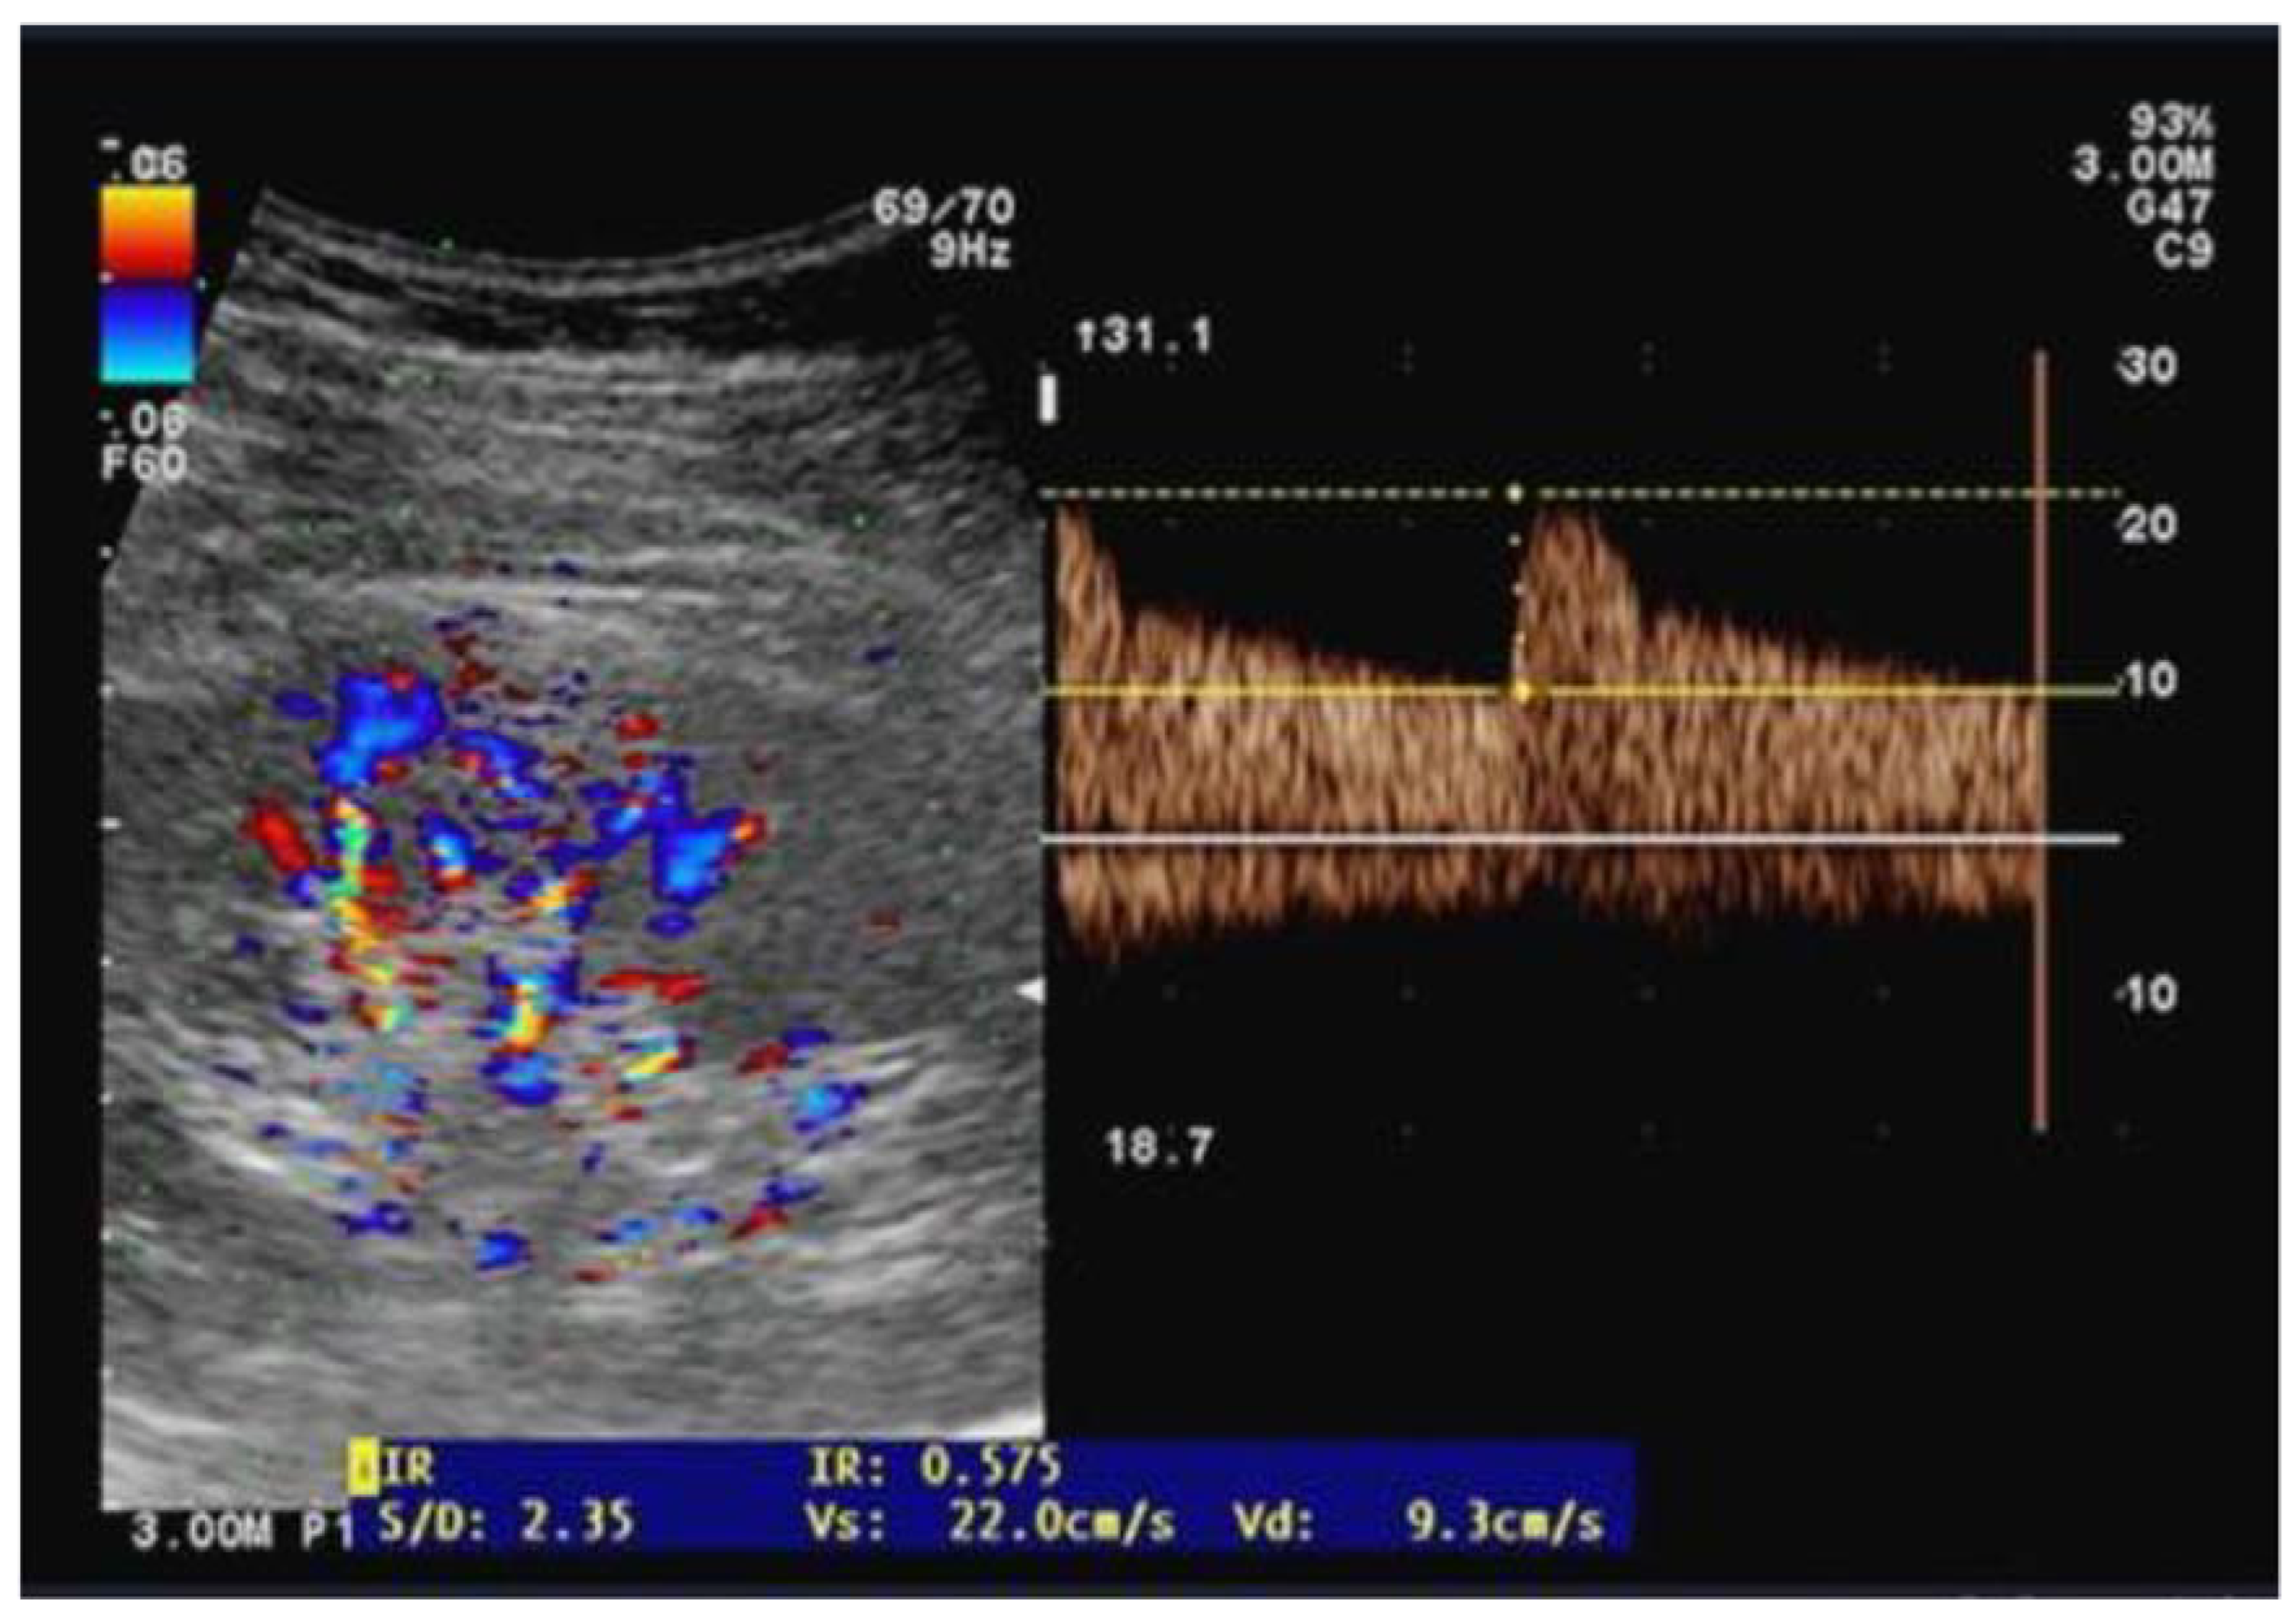

Ultrasound examinations were performed by two independent well-trained sonographers who were not involved in patient care while the anesthesia and ICU physicians were blinded to the results of the renal Doppler measurements. The same operator performed pre- and postoperative examinations on the same patients placed in the supine position and using a CX-50 ultrasound machine with a curvilinear 5 MHz pulsed-wave Doppler flow probe (Philips Healthcare, Eindhoven, Netherland). On each kidney, recordings with the best imaging quality were selected in the longitudinal axis. Pulsed wave Doppler curves in the interlobar or arcuate arteries were recorded with a sample volume of 2–4 mm, three measurements were performed on each kidney and then averaged (Figure 1). The perioperative change in RRI (dRRI) was computed as the ratio of the difference between preoperative and postoperative RRI to postoperative RRI (dRRI = [preoperative RRI—postoperative RRI]/preoperative RRI).

Figure 1. Illustration of an arterial flow measurement using the Doppler pulse velocity to derive the renal resistive index.